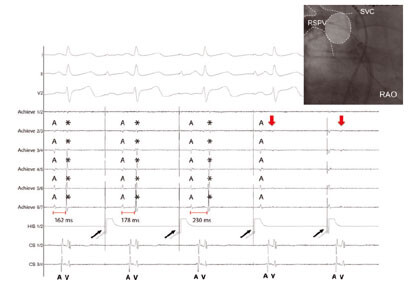

Atrial-Fibrillation

(Abb. 4) Obere Zeile: (links) Katheterpositionen während einer Hochfrequenzstrom Vorhofflimmerablation. (rechts): 3 dimensionale Rekonstruktion des linken Vorhofs nach elektrischer Lungenvenisolation (rote Punkte). Untere Zeile: (links): Katheterposition mit Spiralkatheter in der rechten oberen Lungenvene nach elektrischer Isolation. (rechts): EKG Signale mit elektrophysiologischen Nachweis der elektrischen Isolierung der rechten oberen Lungenvene..